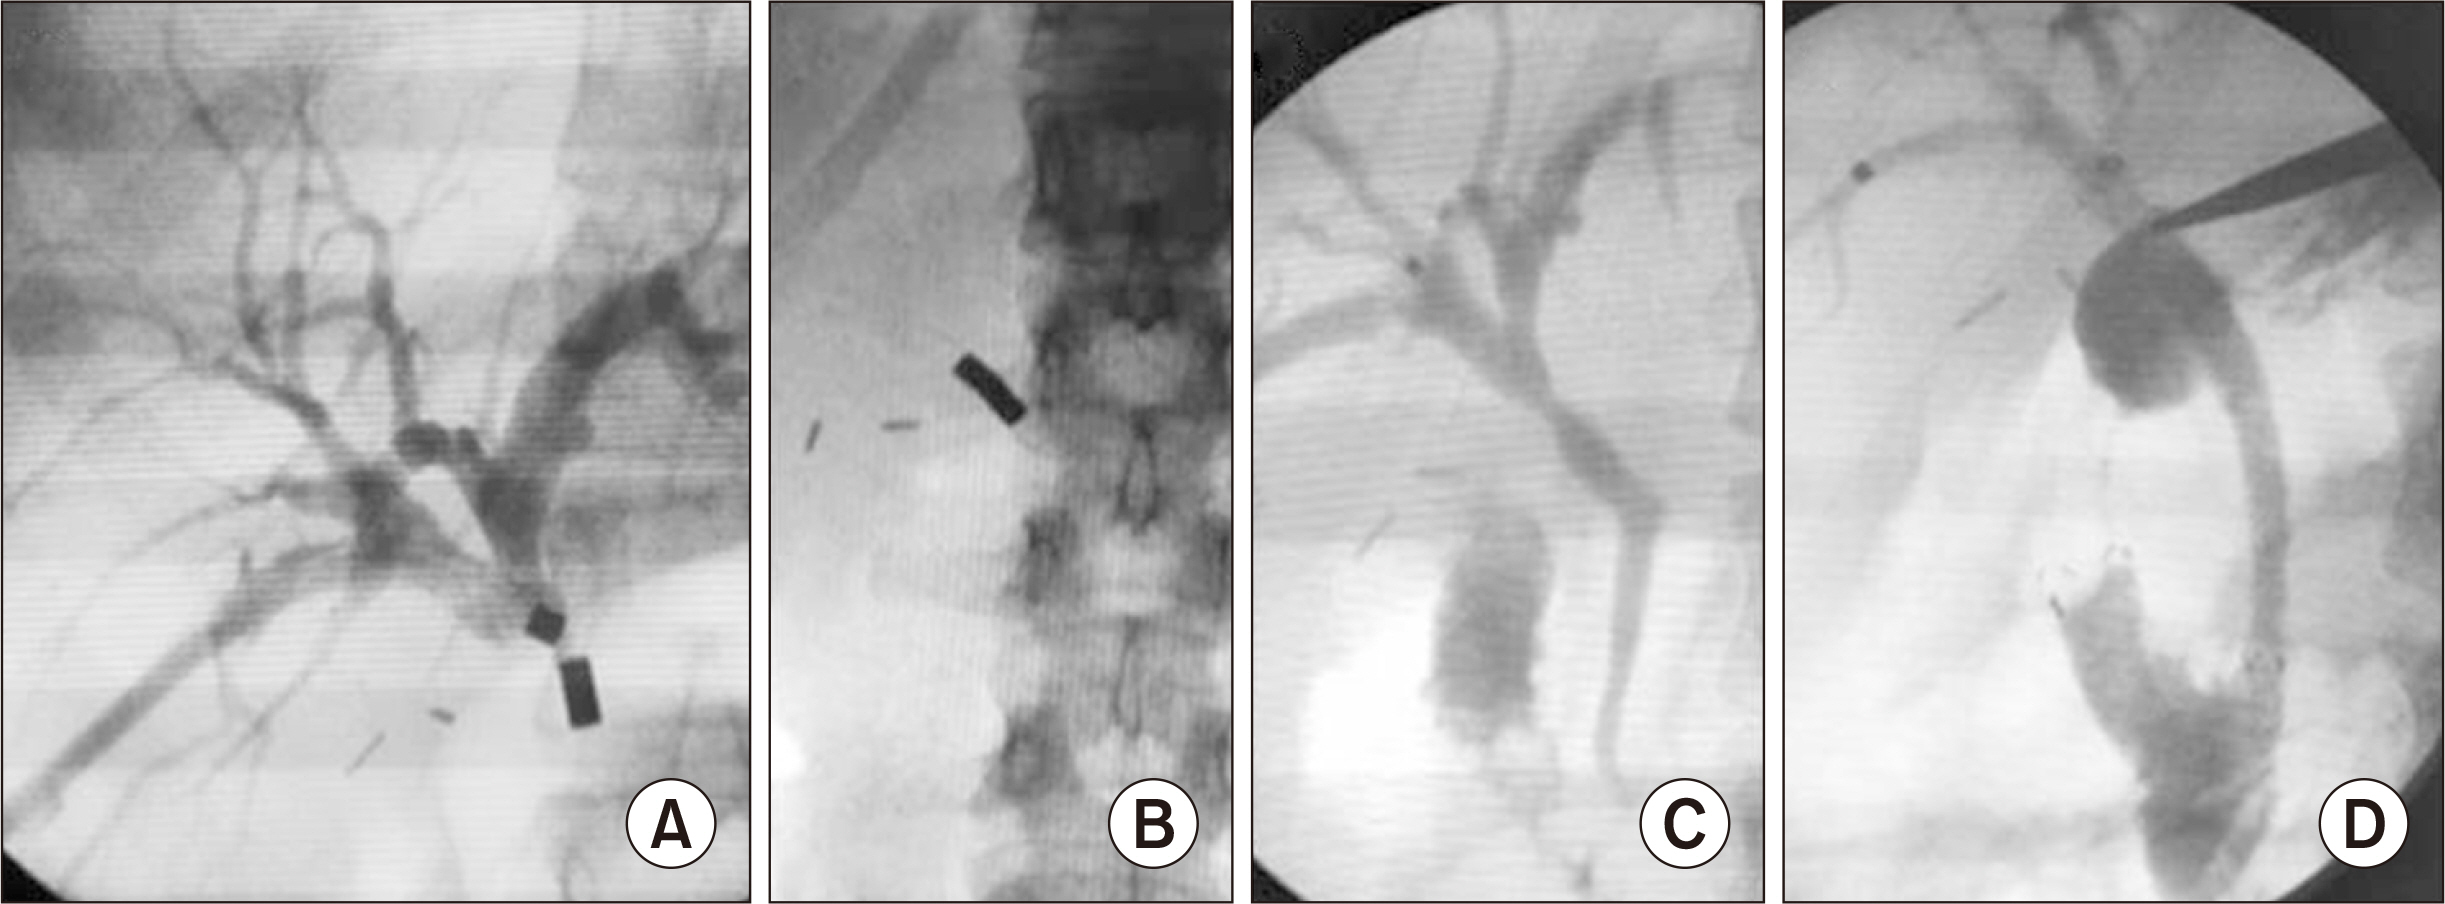

- Bile duct injuries are a serious issue, and their surgical treatment carries the risk of morbidity and mortality. In selected cases, non-surgical treatments are possible, even for total strictures. We outline the technique and results of using magnetic compression anastomosis (MCA) to treat post-cholecystectomy bile duct stricture (PCBDS), in two female patients. Initially, a bilio-cutaneous tract was established via external biliary drainage, followed by the positioning of both endoscopic and percutaneous biliary magnets. After their approximation and subsequent removal, a fully covered self-expandable metal stent (FCSEMS) was deployed across the stricture. The magnet coupling was successfully achieved within the first two weeks of placement. The FCSEMS was maintained for durations of 12 and 16 months. Follow-up durations were 28 and 15 months post-FCSEMS removal. Both patients remain asymptomatic, with normal laboratory and imaging studies, and no adverse events were reported. MCA proves to be a safe and effective method for treating selected cases of total PCBDS. However, further studies and long-term follow-up are required to fully assess the efficacy of this technique.

Article5. Jang SI, Cho JH, Lee DK. 2020; Magnetic compression anastomosis for the treatment of post-transplant biliary stricture. Clin Endosc. 53:266–275. DOI: 10.5946/ce.2020.095. PMID: 32506893. PMCID: PMC7280848.

Article6. Li Y, Sun H, Yan X, Wang S, Dong D, Liu X, et al. 2020; Magnetic compression anastomosis for the treatment of benign biliary strictures: a clinical study from China. Surg Endosc. 34:2541–2550. DOI: 10.1007/s00464-019-07063-8. PMID: 31399950.

Article7. Jang SI, Choi J, Lee DK. 2015; Magnetic compression anastomosis for treatment of benign biliary stricture. Dig Endosc. 27:239–249. DOI: 10.1111/den.12319. PMID: 24905938.

Article15. Jang SI, Rhee K, Kim H, Kim YH, Yun J, Lee KH, et al. 2014; Recanalization of refractory benign biliary stricture using magnetic compression anastomosis. Endoscopy. 46:70–74. DOI: 10.1055/s-0033-1358907. PMID: 24254385.

Article16. Jang SI, Do MY, Lee SY, Cho JH, Joo SM, Lee KH, et al. 2024; Magnetic compression anastomosis for the treatment of complete biliary obstruction after cholecystectomy. Gastrointest Endosc. 100:1053–1060.e1054. DOI: 10.1016/j.gie.2024.05.009. PMID: 38762041.

Article17. Do MY, Jang SI, Cho JH, Joo SM, Lee DK. 2022; Magnetic compression anastomosis for treatment of biliary stricture after cholecystectomy. VideoGIE. 7:253–255. DOI: 10.1016/j.vgie.2022.03.005. PMID: 35815159. PMCID: PMC9264143.

Article18. Ödemiş B, Başpınar B, Tola M, Torun S. 2022; Magnetic compression anastomosis is a good treatment option for patients with completely obstructed benign biliary strictures: a case series study. Dig Dis Sci. 67:4906–4918. DOI: 10.1007/s10620-022-07381-3. PMID: 35050430.